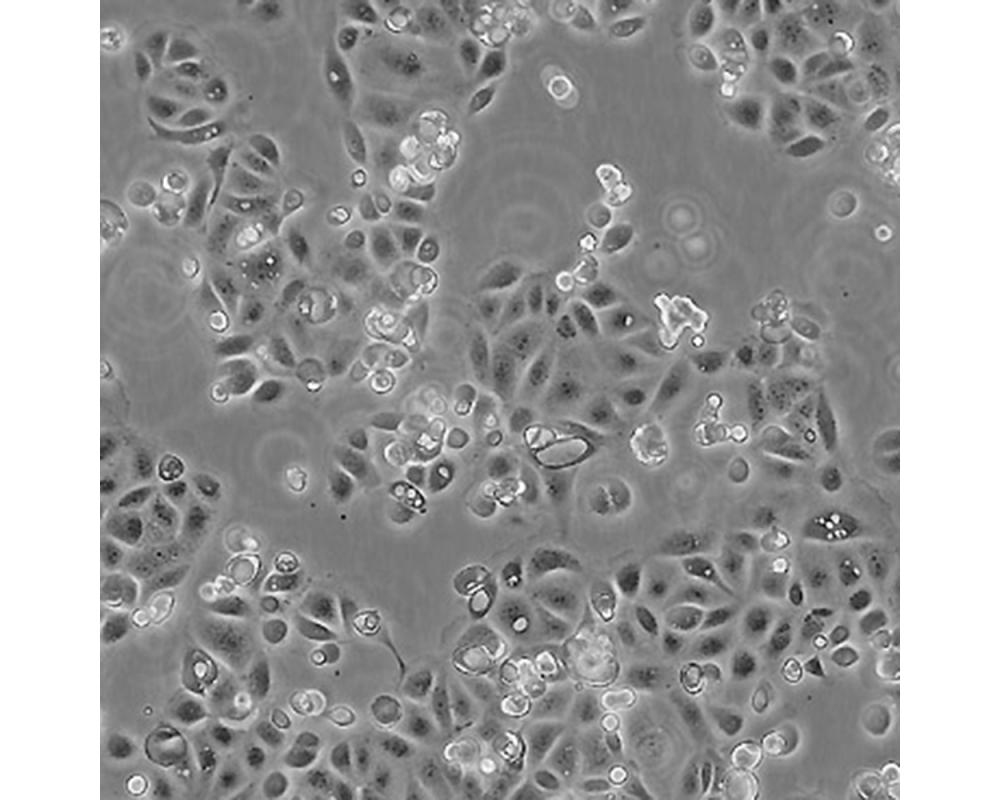

SW1990

產品名稱 SW1990

中文名稱 人胰腺癌細胞

組織來源 胰腺癌;男性

生長特性 貼壁

細胞污染 HIV-1、 HBV、HCV、支原體、細菌、酵母和真菌檢測陰性。

培養基 L15,90%;FBS,10%;雙抗。

傳代方法 1:2-1:4

培養條件 Atmosphere: Air, 95%; CO2, 5%。Temperature: 37℃